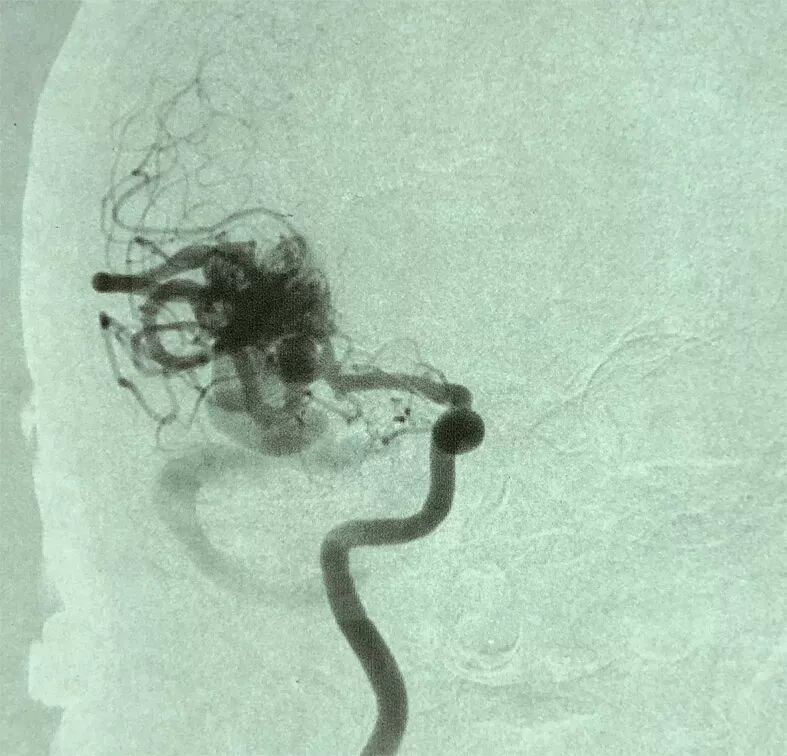

2. 术前DSA示:右侧大脑中动脉主供血AVM,向横窦乙状窦引流,合并多发血流相关性动脉瘤。

AVM合并动脉瘤临床上常采用Redekop方法分为3型:Ⅰ型动脉瘤在AVM内部,为AVM团内型;Ⅱ型为血流相关型,又分为两型:Ⅱa:动脉瘤在AVM主要供血动脉主干的近端,Ⅱb-动脉瘤在AVM供血动脉远端。Ⅲ型动脉瘤与AVM无关。IIa型动脉瘤多需要处理,IIb型动脉瘤位于供血动脉远端,在切除或栓塞AVM后常会消失,一般采用先动态观察,根据发展情况,采取适当的处理策略。

本文报道病例未破裂的AVM合并供血动脉血流相关性动脉瘤,按Redekop分类,本例患者AVM同时伴发供血动脉近端(IIa)及供血动脉远端(IIb)动脉瘤。我们首选在电生理监测下,控制AVM供血的大脑中动脉,采用无出血手术操作技术,沿AVM和周边脑组织分界的胶质增生带分离完整切除AVM。对于伴发的供血动脉血流相关性IIa和IIb动脉瘤采用不同的策略。近端IIa动脉瘤一期显微夹闭处理,远端IIb动脉瘤随访观察的处理策略。手术顺利,术后病人恢复良好,没有功能障碍。